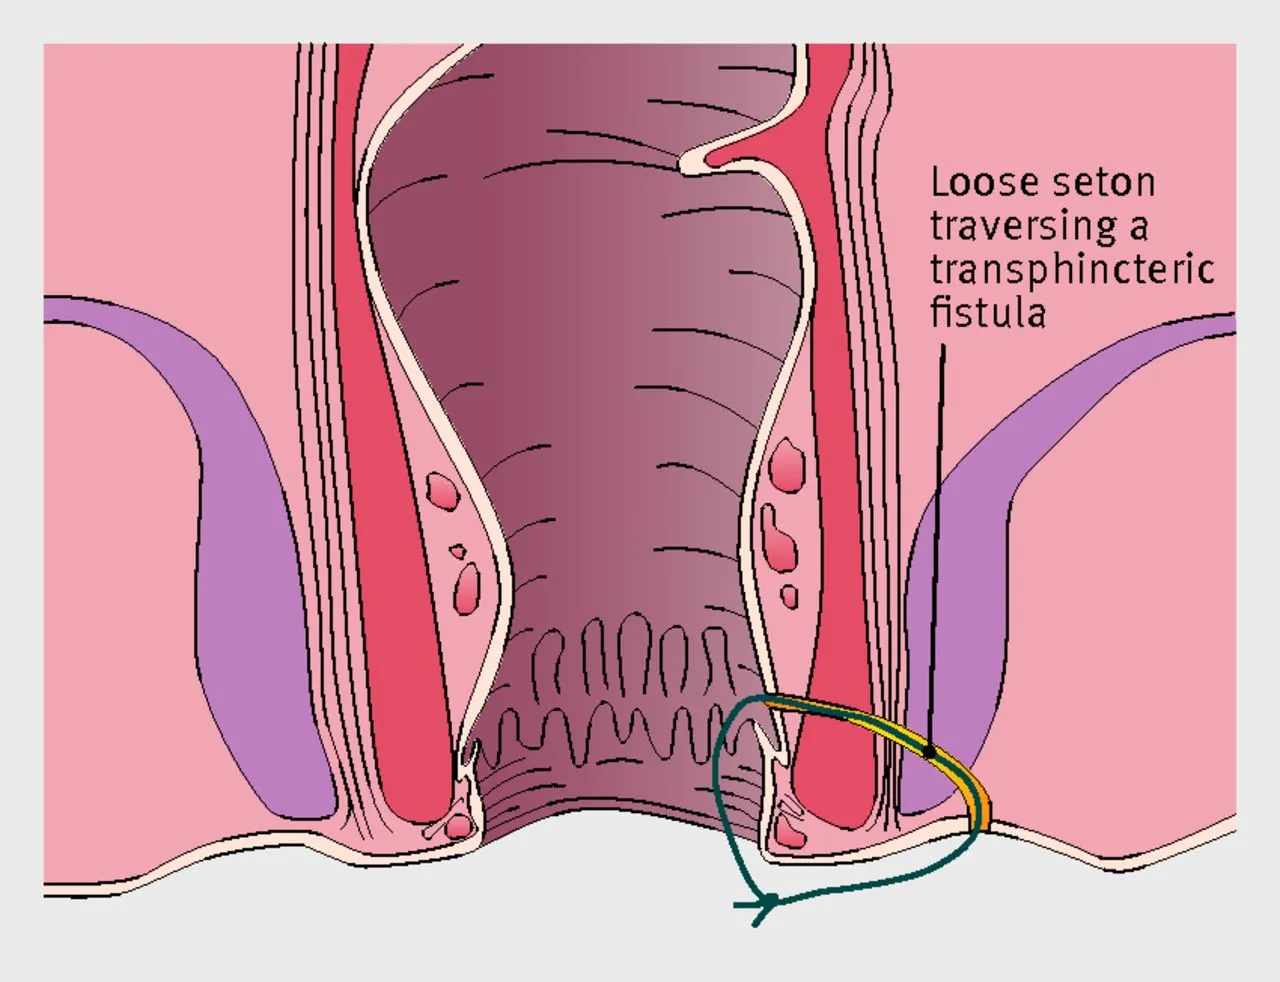

VAAFT (Video-Assisted Anal Fistula Treatment) is a modern, minimally invasive technique used to treat anal fistulas ...

What is VAAFT and How Does It Treat Fistula-in-Ano?

Many patients come to us with a common question: “Doctor, can Anal Fistula …”